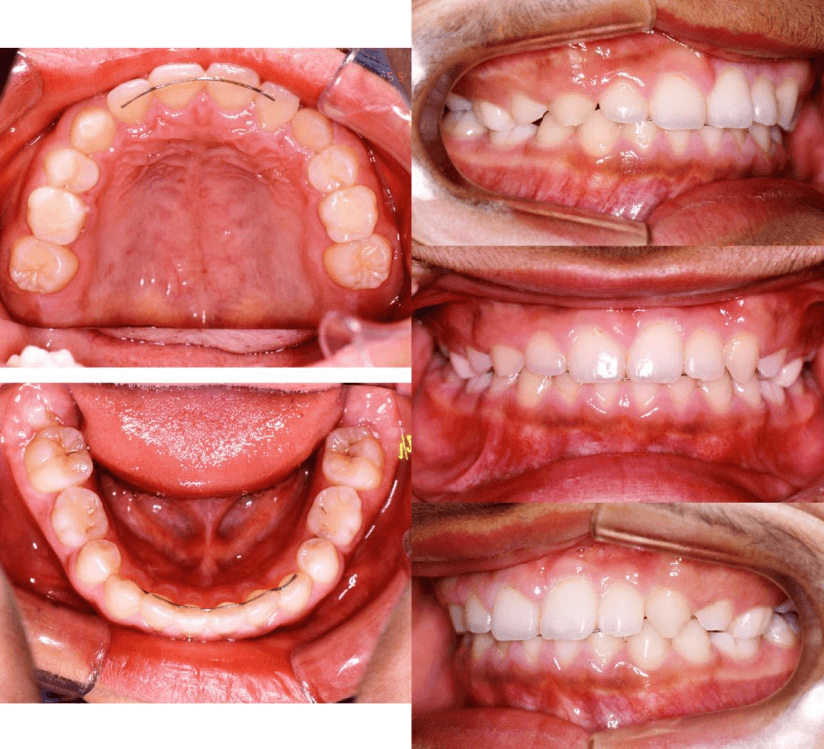

| 年齢・性別 | 8歳9ヶ月の女児 |

|---|---|

| 主訴 | 歯並びの乱れを気にされて来院された患者様です。将来的なスペース不足と歯のねじれ(翼状捻転)が懸念されました。 |

| 治療期間・回数 | 2年10ヶ月・19回 |

| 費用 | 430,000円(税別) |